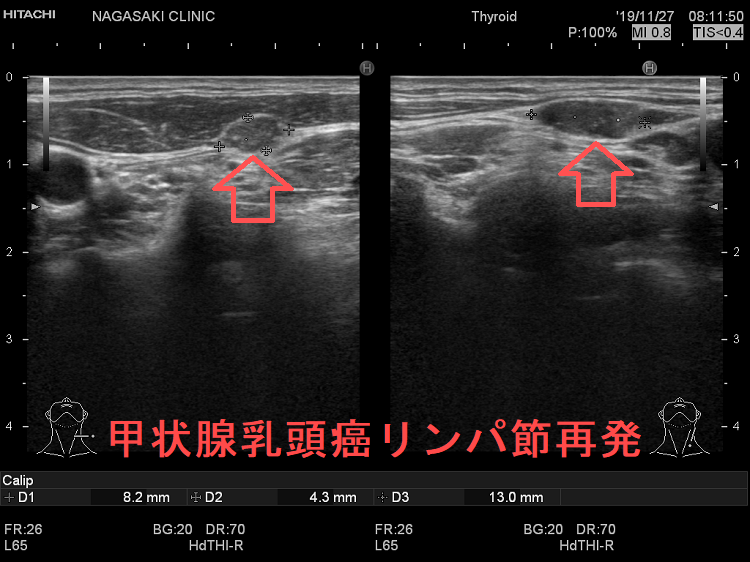

甲状腺乳頭癌のリンパ節再発

甲状腺乳頭癌のリンパ節再発 超音波(エコー)画像

甲状腺乳頭癌のリンパ節再発 超音波(エコー)画像;リンパ門は消失し、砂粒状石灰化が明瞭。

甲状腺乳頭癌のリンパ節再発 超音波ドプラー画像

甲状腺乳頭癌のリンパ節再発 超音波ドプラーモード画像;内部には異常な走行の血管を認め、血流豊富。

甲状腺乳頭癌リンパ節再発 超音波エコー画像

甲状腺乳頭癌のリンパ節再発 超音波エコー画像;リンパ門は消失し、砂粒状石灰化が著明

甲状腺乳頭癌のリンパ節再発(拡大) 超音波エコー画像

甲状腺乳頭癌のリンパ節再発(拡大) 超音波エコー画像;リンパ門は消失し、砂粒状石灰化が著明

甲状腺乳頭癌の同側(切除した側)と対側(切除していない側)のリンパ節再発を同時に認めた症例

次の写真は甲状腺半葉切除(右葉)切除後リンパ節再発です。左右とも総頚動脈外側のリンパ節再発です。

甲状腺乳頭癌の同側(切除した側)のリンパ節再発 超音波(エコー)画像

甲状腺乳頭癌の同側(切除した側)リンパ節再発 超音波(エコー)画像;等エコー、いびつな形で、周囲との境界が一部不明瞭化して浸潤を疑われる。リンパ門は消失し、砂粒状石灰化が著明。

甲状腺乳頭癌の同側(切除した側)のリンパ節再発 超音波(エコー)画像 ドプラーモード

甲状腺乳頭癌の同側(切除した側)リンパ節再発 超音波(エコー)画像 ドプラーモード;内部に異常な走行の血管を認め、血流豊富。

甲状腺乳頭癌 対側(切除していない側)リンパ節再発 超音波(エコー)画像

甲状腺乳頭癌 対側(切除していない側)リンパ節再発 超音波(エコー)画像;等エコー、いびつな形で、周囲との境界が一部不明瞭化して浸潤を疑われる。リンパ門は消失。

甲状腺乳頭癌 対側(切除していない側)リンパ節再発 超音波(エコー)画像 ドプラーモード

甲状腺乳頭癌 対側(切除していない側)リンパ節再発 超音波(エコー)画像  ドプラーモード;内部に異常な走行の血管を認め、血流豊富。